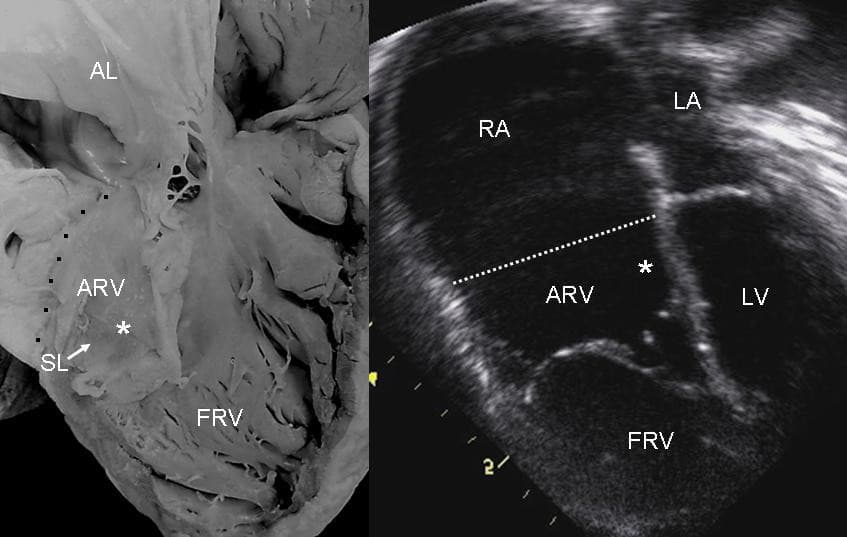

Ebstein's anomaly is a congenital heart defect in which the septal and posterior leaflets of the tricuspid valve are displaced downwards towards the apex of the right ventricle of the heart. It is classified as a critical congenital heart defect accounting for less than 1% of all congenital heart defects presenting in around 1 per 200,000 live births. Ebstein's anomaly usually presents with a systolic murmur (sometimes diastolic) and frequently with a gallop rhythm. The annulus of the valve is still in the normal position. The valve leaflets, however, are to a varying degree, attached to the walls and septum of the right ventricle. A subsequent "atrialization" of a portion of the morphologic right ventricle (which is then contiguous with the right atrium) is seen. This causes the right atrium to be large and the anatomic right ventricle to be small in size. S3 heart sound S4 heart sound Triple or quadruple gallop due to widely split S1 and S2 sounds plus a loud S3 and/or S4 Systolic murmur of tricuspid regurgitation = Holosystolic or early systolic murmur along the lower left sternal border depending on the severity of the regurgitation Right atrial hypertrophy Right ventricular conduction defects Wolff-Parkinson-White syndrome often accompanies While Ebstein's anomaly is defined as the congenital displacement of the tricuspid valve towards the apex of the right ventricle, it is often associated with other abnormalities. Typically, anatomic abnormalities of the tricuspid valve exist, with enlargement of the anterior leaflet of the valve. The other leaflets are described as being plastered to the endocardium. Tethering the underlying ventricular wall is the most common for the posterior and septal leaflets, and sail-like anterior leaflets may be tethered to the RV free wall also. About 50% of individuals with Ebstein's anomaly have an associated shunt between the right and left atria, either an atrial septal defect or a patent foramen ovale.